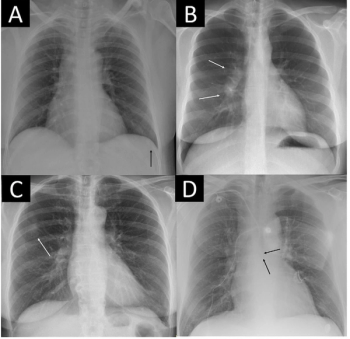

Adjunctive use of the AI-powered software led to an average 38.6 percent increase in the detection of pneumothorax by general radiologists, according to a 2023 study.

For clinically actionable pneumothorax, an artificial intelligence algorithm demonstrated a 93 percent AUC and a 96 percent specificity rate in a study involving chest X-rays from over 27,000 adults.

The AI-powered AZchest CXR software reportedly offers 93.79 percent sensitivity and a 98.57 percent AUC for pneumothorax.